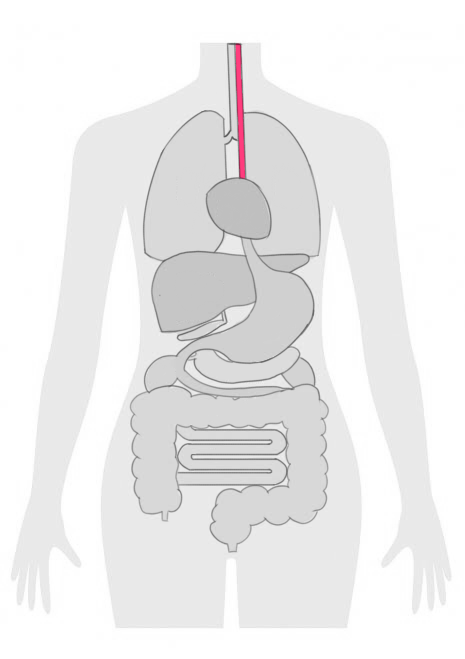

食道がんは、食道の内側の細胞が異常に増殖することで発生するがんの一種です。

しかし、進行が進むと食事の際の痛みや嚥下困難などの症状が現れることがあります。

末期の食道がんは、がんが食道の壁を超えて周囲の組織やリンパ節に広がっている状態を指します。

また、食道がんの早期発見のための検査方法として、内視鏡検査が行われることが多いです。